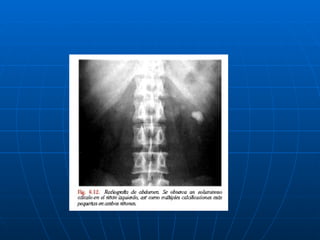

APENDICITIS AGUDA EXAMENES RADIOLOGICOS : Radiografías Simples de Abdomen (no hay signos patognomónicos): 1.-Niveles de líquido ubicados en el ciego e ileon terminal (asa centinela en ileon). 2.- Ileo localizado (gas en ciego, colon ascendente o ileon terminal), 3.- Mayor densidad de tejidos blandos (F.i.d) 4.- Presencia de fecalito en FI.D.

APENDICITIS AGUDA 5.- Borramiento de la banda del flanco derecho, línea radiolúcida producida por  la grasa entre el peritoneo y transverso del abdomen. 6.- Borramiento de la sombra del Psoas Derecho. 7.- Apéndice lleno de gas. 8.- Gas intraperitoneal libre ENEMA DE BARIO (Pacientes con elevado riesgo quirúrgico)

APENDICITIS AGUDA EXAMENESRADIOLOGICOS : Radiografías Simples de Abdomen (no hay signos patognomónicos): 1.-Niveles de líquido ubicados en el ciego e ileon terminal (asa centinela en ileon). 2.- Ileo localizado (gas en ciego, colon ascendente o ileon terminal), 3.- Mayor densidad de tejidos blandos (F.i.d) 4.- Presencia de fecalito en FI.D.

APENDICITIS AGUDA 5.-Borramiento de la banda del flanco derecho, línea radiolúcida producida por la grasa entre el peritoneo y transverso del abdomen. 6.- Borramiento de la sombra del Psoas Derecho. 7.- Apéndice lleno de gas. 8.- Gas intraperitoneal libre ENEMA DE BARIO (Pacientes con elevado riesgo quirúrgico)